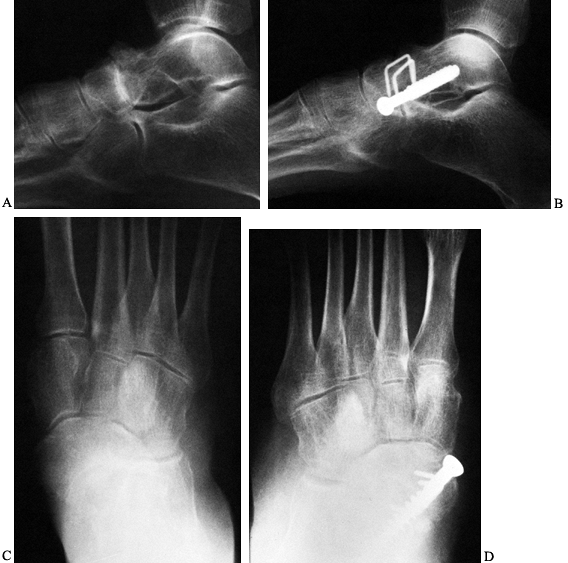

general rule, fusion occurs by 12 to 16 weeks (Fig. 115.6).

Figure 115.6. Talonavicular arthrodesis using 6.5-mm screw and two small staples. A: Arthrosis of the talonavicular joint. B: Method of internal fixation. C: Degenerative arthritis of the talonavicular joint, anteroposterior radiograph. D: Fixation of talonavicular joint using compression screw and staple.

Fusion usually occurs by 12 to 16 weeks (Fig. 115.7).

Figure 115.7. AP (A) and lateral (B) radiographs following a double arthrodesis utilizing 4.0-mm cannulated screws.